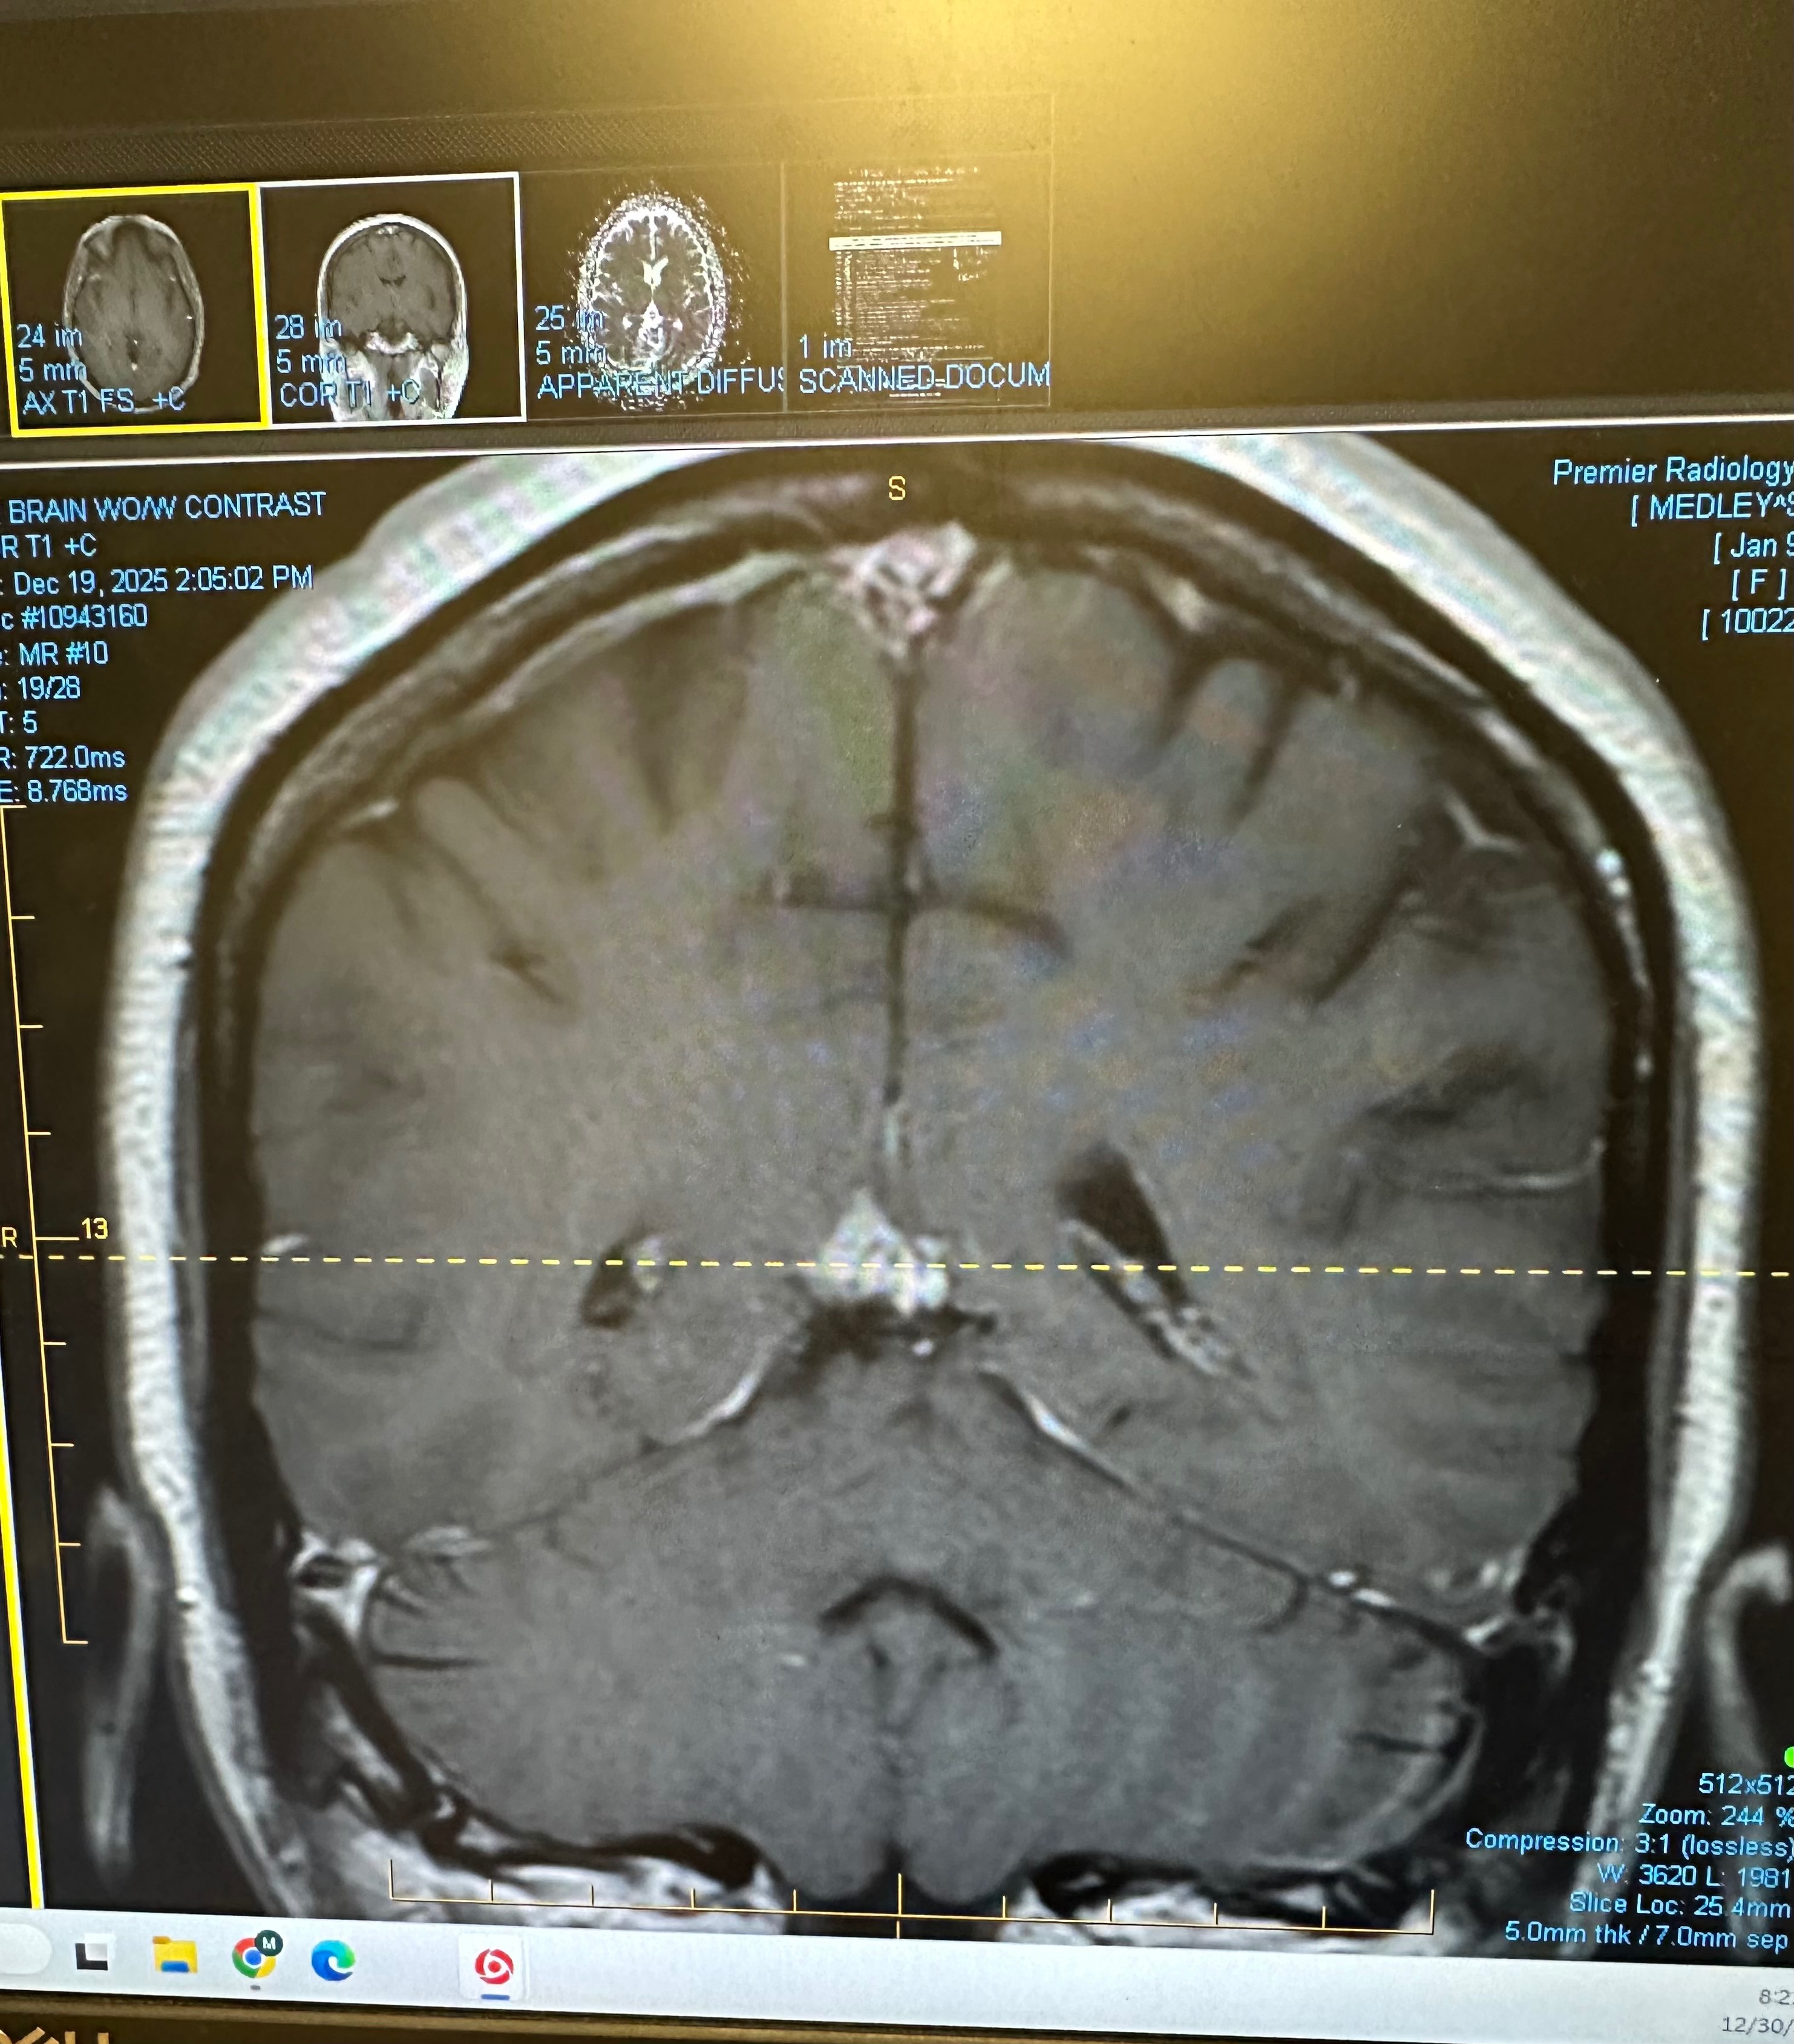

My name is Sarah, and I’m reaching out during one of the most challenging times of my life. Around Thanksgiving, I received two life-changing diagnoses just weeks apart: an inoperable brain tumor and a breast mass. While these two conditions are unrelated, they have both brought a wave of uncertainty and fear into my world. Since then, my days have been filled with countless medical appointments, tests, scans, imaging, and procedures. The process of getting answers has required me and my loved ones to miss work and has brought mounting medical expenses that I am no longer able to keep up with on my own. I have lost traction despite doing everything I can to manage these costs myself.